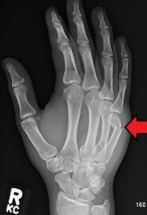

♦ 엑스레이(X-ray) 촬영: 복서 골절은 다섯 번째 중수골 경부 골절이므로, 여러 각도에서 손과 손등의 엑스레이를 촬영하여 골절 여부와 골절선의 위치, 골절의 변형 정도를 명확히 확인합니다. 일반적으로 엑스레이로 쉽게 진단이 가능합니다.

♦ 정의: 다섯 번째(새끼손가락) 중수골의 경부 부위가 부러지는 골절. 때로 네 번째(약지) 중수골에도 발생할 수 있습니다.

복서 골절(Boxer's fracture)은 주먹 쥔 손으로 딱딱한 물체(벽, 펀치볼 등)를 가격할 때 주로 발생하는 손의 다섯 번째 중수골(새끼손가락 쪽) 경부의 골절입니다. 이름은 '복서(권투 선수)"에서 따왔으나 실제 권투 선수보다는 일반 젊은 남성들에게서 분노나 실수로 벽을 치다가 자주 발견됩니다.